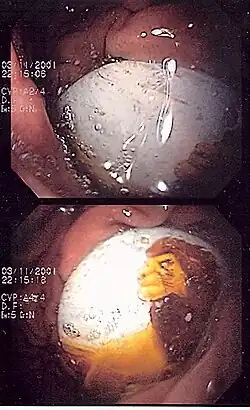

Small toys may be swallowed by children, such as this electronic button seen in a child's stomach. Toys stuck in the esophagus or too large to pass through the stomach may need to be removed with endoscopes.